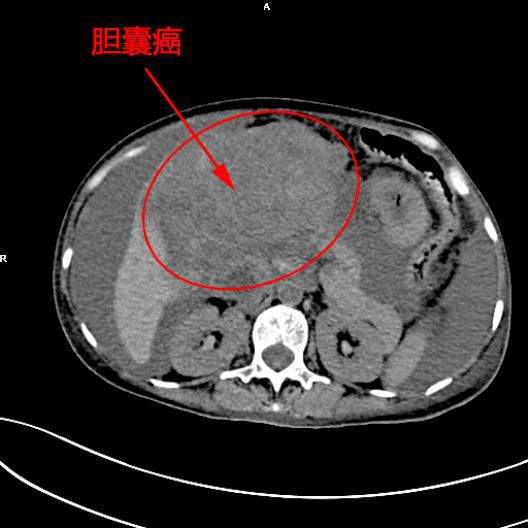

患者陳女士,57歲,汕頭潮南人,2個月前出現右上腹痛,在汕頭大型三甲醫院确診爲膽囊癌,因腫瘤爲晚期,已擴散至肝髒、十二指腸,患者放棄在汕頭治療,回家後自行采用中藥治療。近期右上腹痛加重,反複排黑便,遂來我院住院,診斷爲膽囊癌伴活動性出血。

5月11日下午,内三科主任李旭丹、影像科副主任胡志華上台施術。通過粵東領先的飛利浦DSA造影顯示,患者腫瘤供血血管豐富,膽囊動脈造影可見腫瘤染色明顯,有造影劑外溢,提示部分血管末梢有破裂出血現象,探查胃十二指腸動脈及腸系膜上動脈未見出血征像,豐富的血供使腫瘤能獲取大量的營養快速生長,血管末梢的破裂出血導緻患者反複黑便。